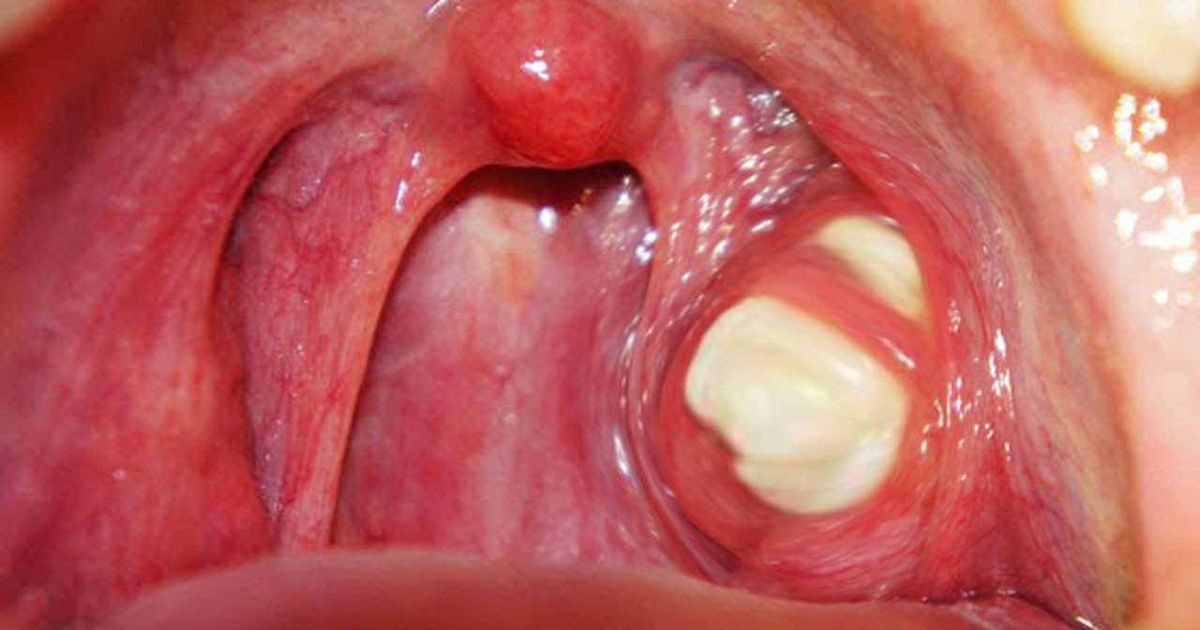

A Lump in the Neck

A lump developing in an individual's neck could indicate an enlarged lymph node., which is a common warning sign in both mouth and oropharyngeal cancers. If the lump is red, hot, or painful, it could mean an infection has developed and it is probably not cancerous. The same is true for lumps that come and go. When a lump is cancerous, it generally forms and grows slowly. Some individuals also experience a lump on their lip, in their mouth, or throat.